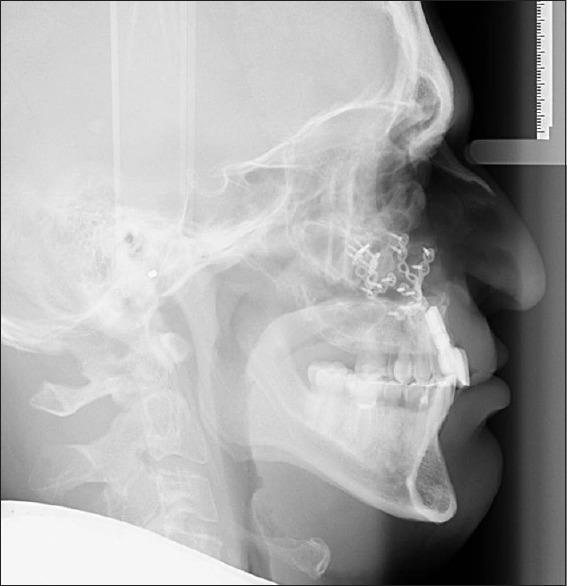

Two adult male cleft lip and palate patients were treated with maxillary distraction osteogenesis in two stages. In the first stage, surgically assisted rapid palatal expansion with a tooth-borne device was performed to significantly expand the maxillary arch in the transverse dimension. After the teeth were orthodontically aligned, the horizontal distraction of the maxilla was made by two internal maxillary distraction devices.

In the first patient, the maxilla was initially widened by 11 mm and then distracted forward by 20 mm. Despite the breakage of the shaft of one of the two distractors at the end of distraction, a satisfactory occlusion was found at the time of distractor device removal. The maxillary position has remained stable through 8 years of follow-up. In the second patient, the palate was widened by 14 mm and the maxilla was distracted forward by 22 mm. The maxillary position has remained stable through 3 years of follow-up.